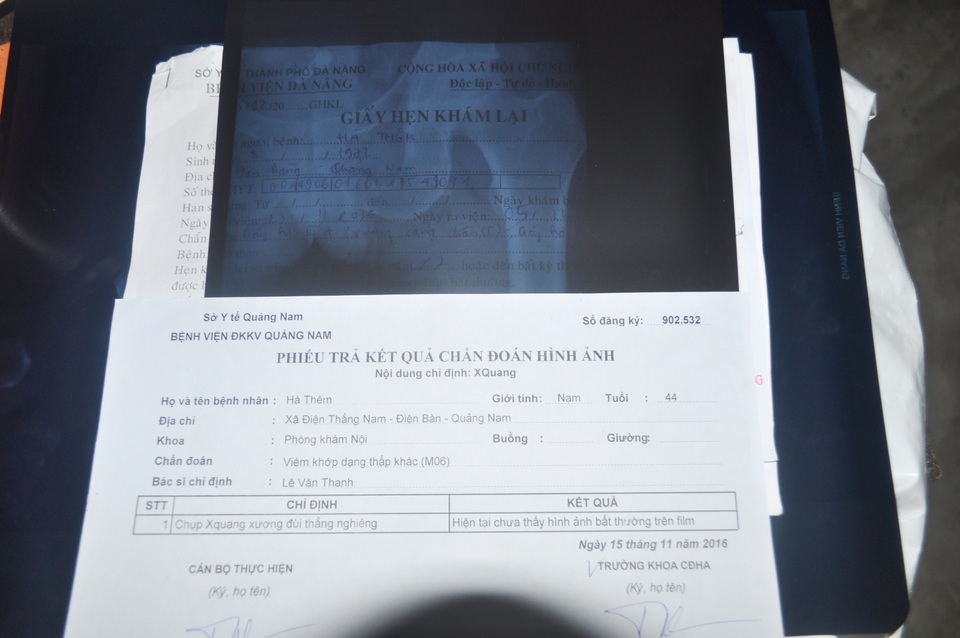

Cách đây hơn 1 năm, anh Hà Thêm (SN 1972, trú thôn Ngũ Đông, xã Điện Thắng Nam, thị xã Điện Bàn, Quảng Nam) phát hiện mình bị thoái hoá xương đùi nhưng không có tiền chữa trị. Tình trạng bệnh ngày càng trầm trọng, việc di chuyển dần trở nên khó khăn, đau nhức thường xuyên khiến cơ thể anh suy nhược.

Nhưng bi kịch vẫn chưa hồi kết thúc khi cách đây gần một tháng anh được người thân chở đi trên đường thì va chạm với xe máy của một thanh niên say xỉn. Sau tai nạn, anh nằm liệt một chỗ, mọi sinh hoạt cá nhân đều phải nhờ vợ, mẹ già và những người hàng xóm tốt bụng xung quanh. Một chân bị thoái hóa xương đùi ngày càng trầm trọng, nay lại thêm gãy xương cổ tay và gãy xương ống chân cần phải phẫu thuật nếu không anh có thể vĩnh viễn mất đi hai chân của mình.